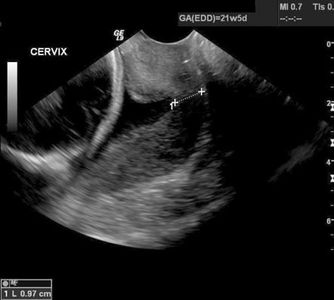

The closed cervix should measure at least 30 mm at this time- and is often over 40 mm (Caution: a full urinary bladder or focal uterine contraction can elongate the perceived cervical length and make it appear longer than it really is).

A shortened cervix indicates a higher risk for preterm delivery with the highest risk of extreme prematurity for patients with cervical length of less than 20 mm. Read more about prematurity, prevention and treatment.

Cervical shortening and/ or dilatation usually does not occur until after 18 weeks, simply because there isn't enough weight from the pregnancy to test it before then. Any bleeding after 16-18 weeks should be taken seriously because it could indicate cervical shortening or dilatation.